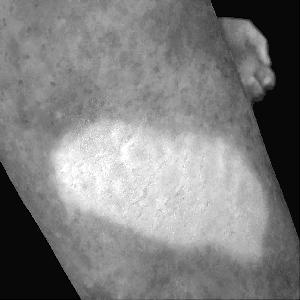

Figure 2a. illustrates the information retrieved from this CNN model from various layers of the architecture that is used to create a BAM map, which is used to segment the burn injury from normal skin in a 2D image. First, the heatmaps for the activations of the first convolutional layer are computed (Figure 2a(ii)), and then Grad-CAM heatmap is computed using the last convolutional layer (Figure 2a(iii)). Once the first convolutional layer heatmaps and Grad-CAM are generated, the algorithm uses a three-round iterative process to select activation heatmaps that have the highest correlation to the Grad-CAM heatmap among the channels of the first layer activations. After the process of correlating and selecting heatmaps is completed (Figure 3 ), segmentation masks are created next (Figure 4). A final composite BAM mask is created as illustrated in 2b(i). Finally, figure 2b (ii-iii) illustrates how the BAM mask is superimposed on the input image to segment the burn injury area, and how edge detection may be applied to the BAM mask in order to obtain a fine-tuned segmented boundary superimposed on the input image.

Figure 5 shows several burn image examples of patients with different sized burns in different body locations, for which the Grad-CAM heatmap, BAM heatmap, BAM masks, and final superimposed images were created. These results allow us to understand the clinical accuracy of burn segmentation from 2D images using BAM. These images show various degrees of burn. It is evident from the results that given skin burn images and the corresponding Grad-CAM heatmaps highlighting the burn regions even partially, the BAM heatmap is able to highlight the burn regions and display a high resolution heatmap accurately. This is the main contribution of BAM. It can be seen from the figure that the BAM heatmaps display different contrast levels in highlighting the burn regions. More precisely, the more superficial burns are highlighted with a lower contrast to the normal skin. The deeper burns, on the other hand, are highlighted with a higher contrast to the normal skin. Nevertheless, the contrast between the burn regions and the normal skin in the BAM heatmaps is sufficient for generating the binary segmentation masks even for the more superficial burns. As evidenced, the BAM heatmaps can successfully be converted into accurate binary segmentation masks. The rightmost column of the figure shows the BAM segmentation masks on top of the input images in order to better visualize the effectiveness of BAM in segmenting the burn regions. In short, comparing the Grad-CAM heatmaps against the BAM heatmaps and BAM segmentation masks provides evidence for a significant improvement in generating heatmaps that are both class-discriminative and fine-grained.